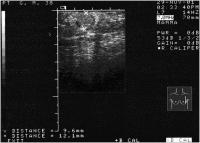

Fallbericht: Ein ungewöhnlicher Fall eines solitären Knotens in der Brust als Erstmanifestation eines anaplastischen Schilddrüsenkarzinoms